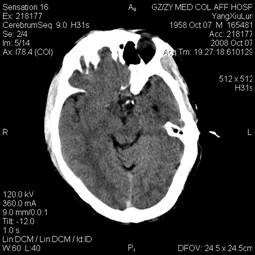

In October 2008, a 50-year-old man presented with progressive fever, headache, nausea and vomiting for five days. On physical examination, the temperature was 39 ℃, blood pressure (BP) was 86/60 mm Hg, bulbar conjunctiva was congestive. But his neurological system and other systemic examinations were unremarkable. His white blood cell was 23×109/L, haemoglobin was 166g/L, blood platelet was 79×109/L, urea was 16.85 mmol/L, creatinine was 291 umol/L and uric acid was 496 umol/L. The results of prothrombin time (PT), activate part blood coagulation time (APTT), thrombin time (TT) and fibrinogen (FIG) were in normal range. Both hepatitis B and C virus test were negative. Cerebral computed tomography (CT) scan was normal (Fig. 1). The electroencephalogram showed slight abnormality, and both intracranial pressure and cerebrospinal fluid were normal. The patient was diagnosed and treated as viral encephalitis. However, seven days later, his headache became more and more serious and the second cerebral CT presented SAH (Fig. 2), but there was no remarkable finding on neurological examination. The next day, he presented neck rigidity. Therefore, intracranial vascular digital subtraction angiography (DSA) was carried out to find out the cause of SAH. However, the result of DSA was unremarkable (Fig. 3A and B). In order to find out the pathogen, we consulted a doctor for infectious diseases; she considered it to be EHF and suggested us to detect the serum antibody EHF-IgM and EHF-IgG, and both results were positive by indirect immunofluorescence in our central laboratory.

Figure 1

Non-anomalous findings of head CT.

Figure 2

Diffused high-density video in the bilateral subarachnoid space on repeat head CT seven days later.